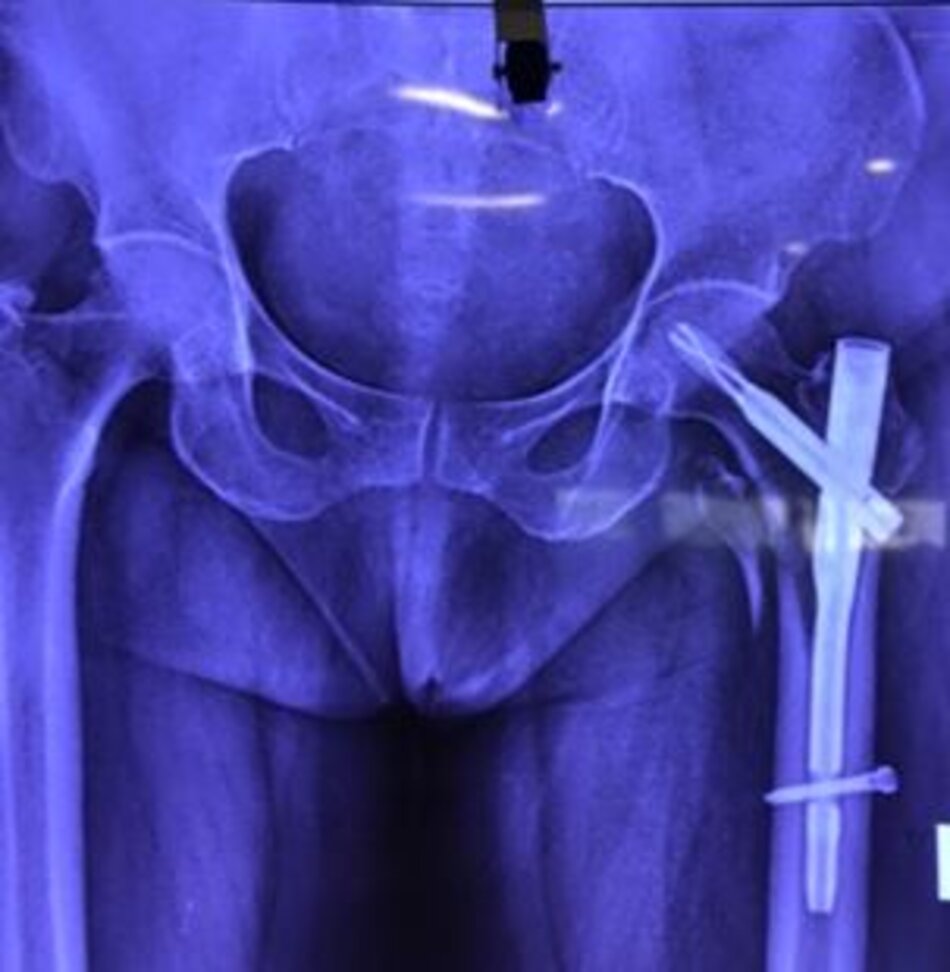

Xquang trước mổBN 101 tuổi, gãy cổ xương đùi/ loãng xương nặng

Xquang trước mổ. BN 101 tuổi, gãy cổ xương đùi/ loãng xương nặng

Xquang sau mổBệnh nhân được ngồi dậy ngay sau mổ, tập đi sau mổ 1 tuần

Xquang sau mổ. Bệnh nhân được ngồi dậy ngay sau mổ, tập đi sau mổ 1 tuần